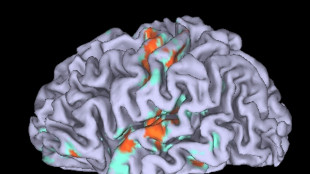

Cervello,in migliaia di immagini l'atlante 3D delle connessioni

Cervello,in migliaia di immagini l'atlante 3D delle connessioni